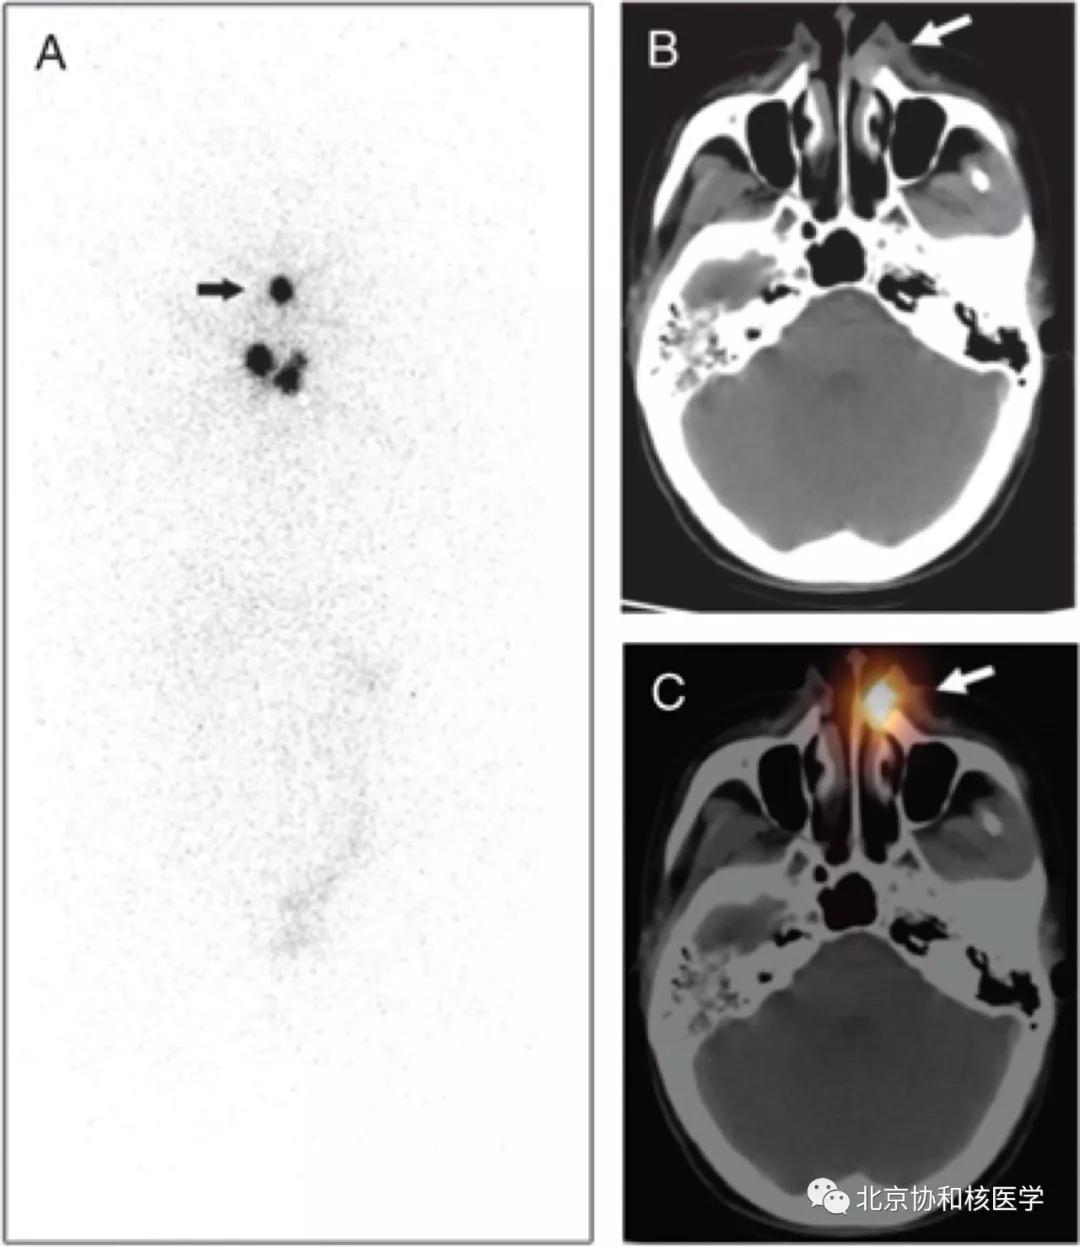

脑膜瘤所致碘摄取:

鼻骨骨样骨瘤所致碘摄取,腹部另可见由于巨大肾囊肿所致碘异常摄取: